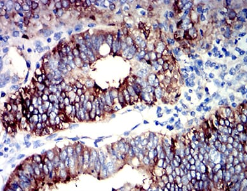

PIGR Mouse Monoclonal antibody[1E2B1]

IHC    1/200 - 1/1000